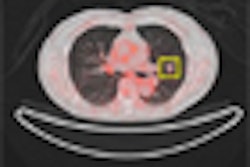

Speaking of cancer, reviewing FDG-PET scans of non-small cell lung cancer patients before radiation therapy may lead to significant changes in treatment strategy and radiation therapy planning, according to a study from French researchers.

Meanwhile, international editor Eric Barnes reports on Japanese researchers who have developed computer-aided detection (CAD) software that detects lung nodules in PET/CT images of lung cancer screening patients. Applying a combined CAD system to both modalities, instead of CT or PET alone, nearly doubled the number of solitary pulmonary nodules detected.